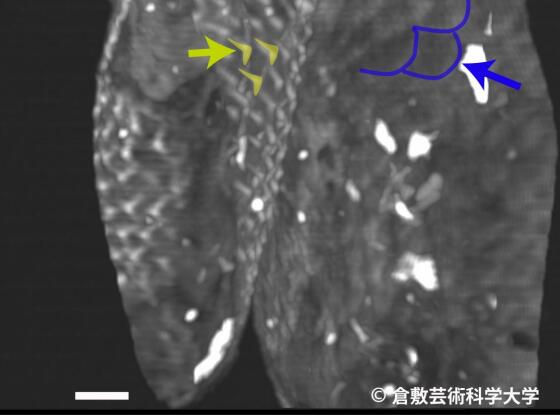

研究员使用扫描电子显微镜观察木乃伊脱落的毛发,发现其表面竟有与哺乳类动物一样的角质层,至于下半身,人鱼木乃伊拥有背鳍,而腹部、臀部和尾巴都被鳞片覆盖,但上半身的鳞片却与下半身不同,进行X光摄影检查和电脑断层扫描发现,人鱼颈部和背鳍部位分别插了一根针,也让研究人员感到相当困惑。